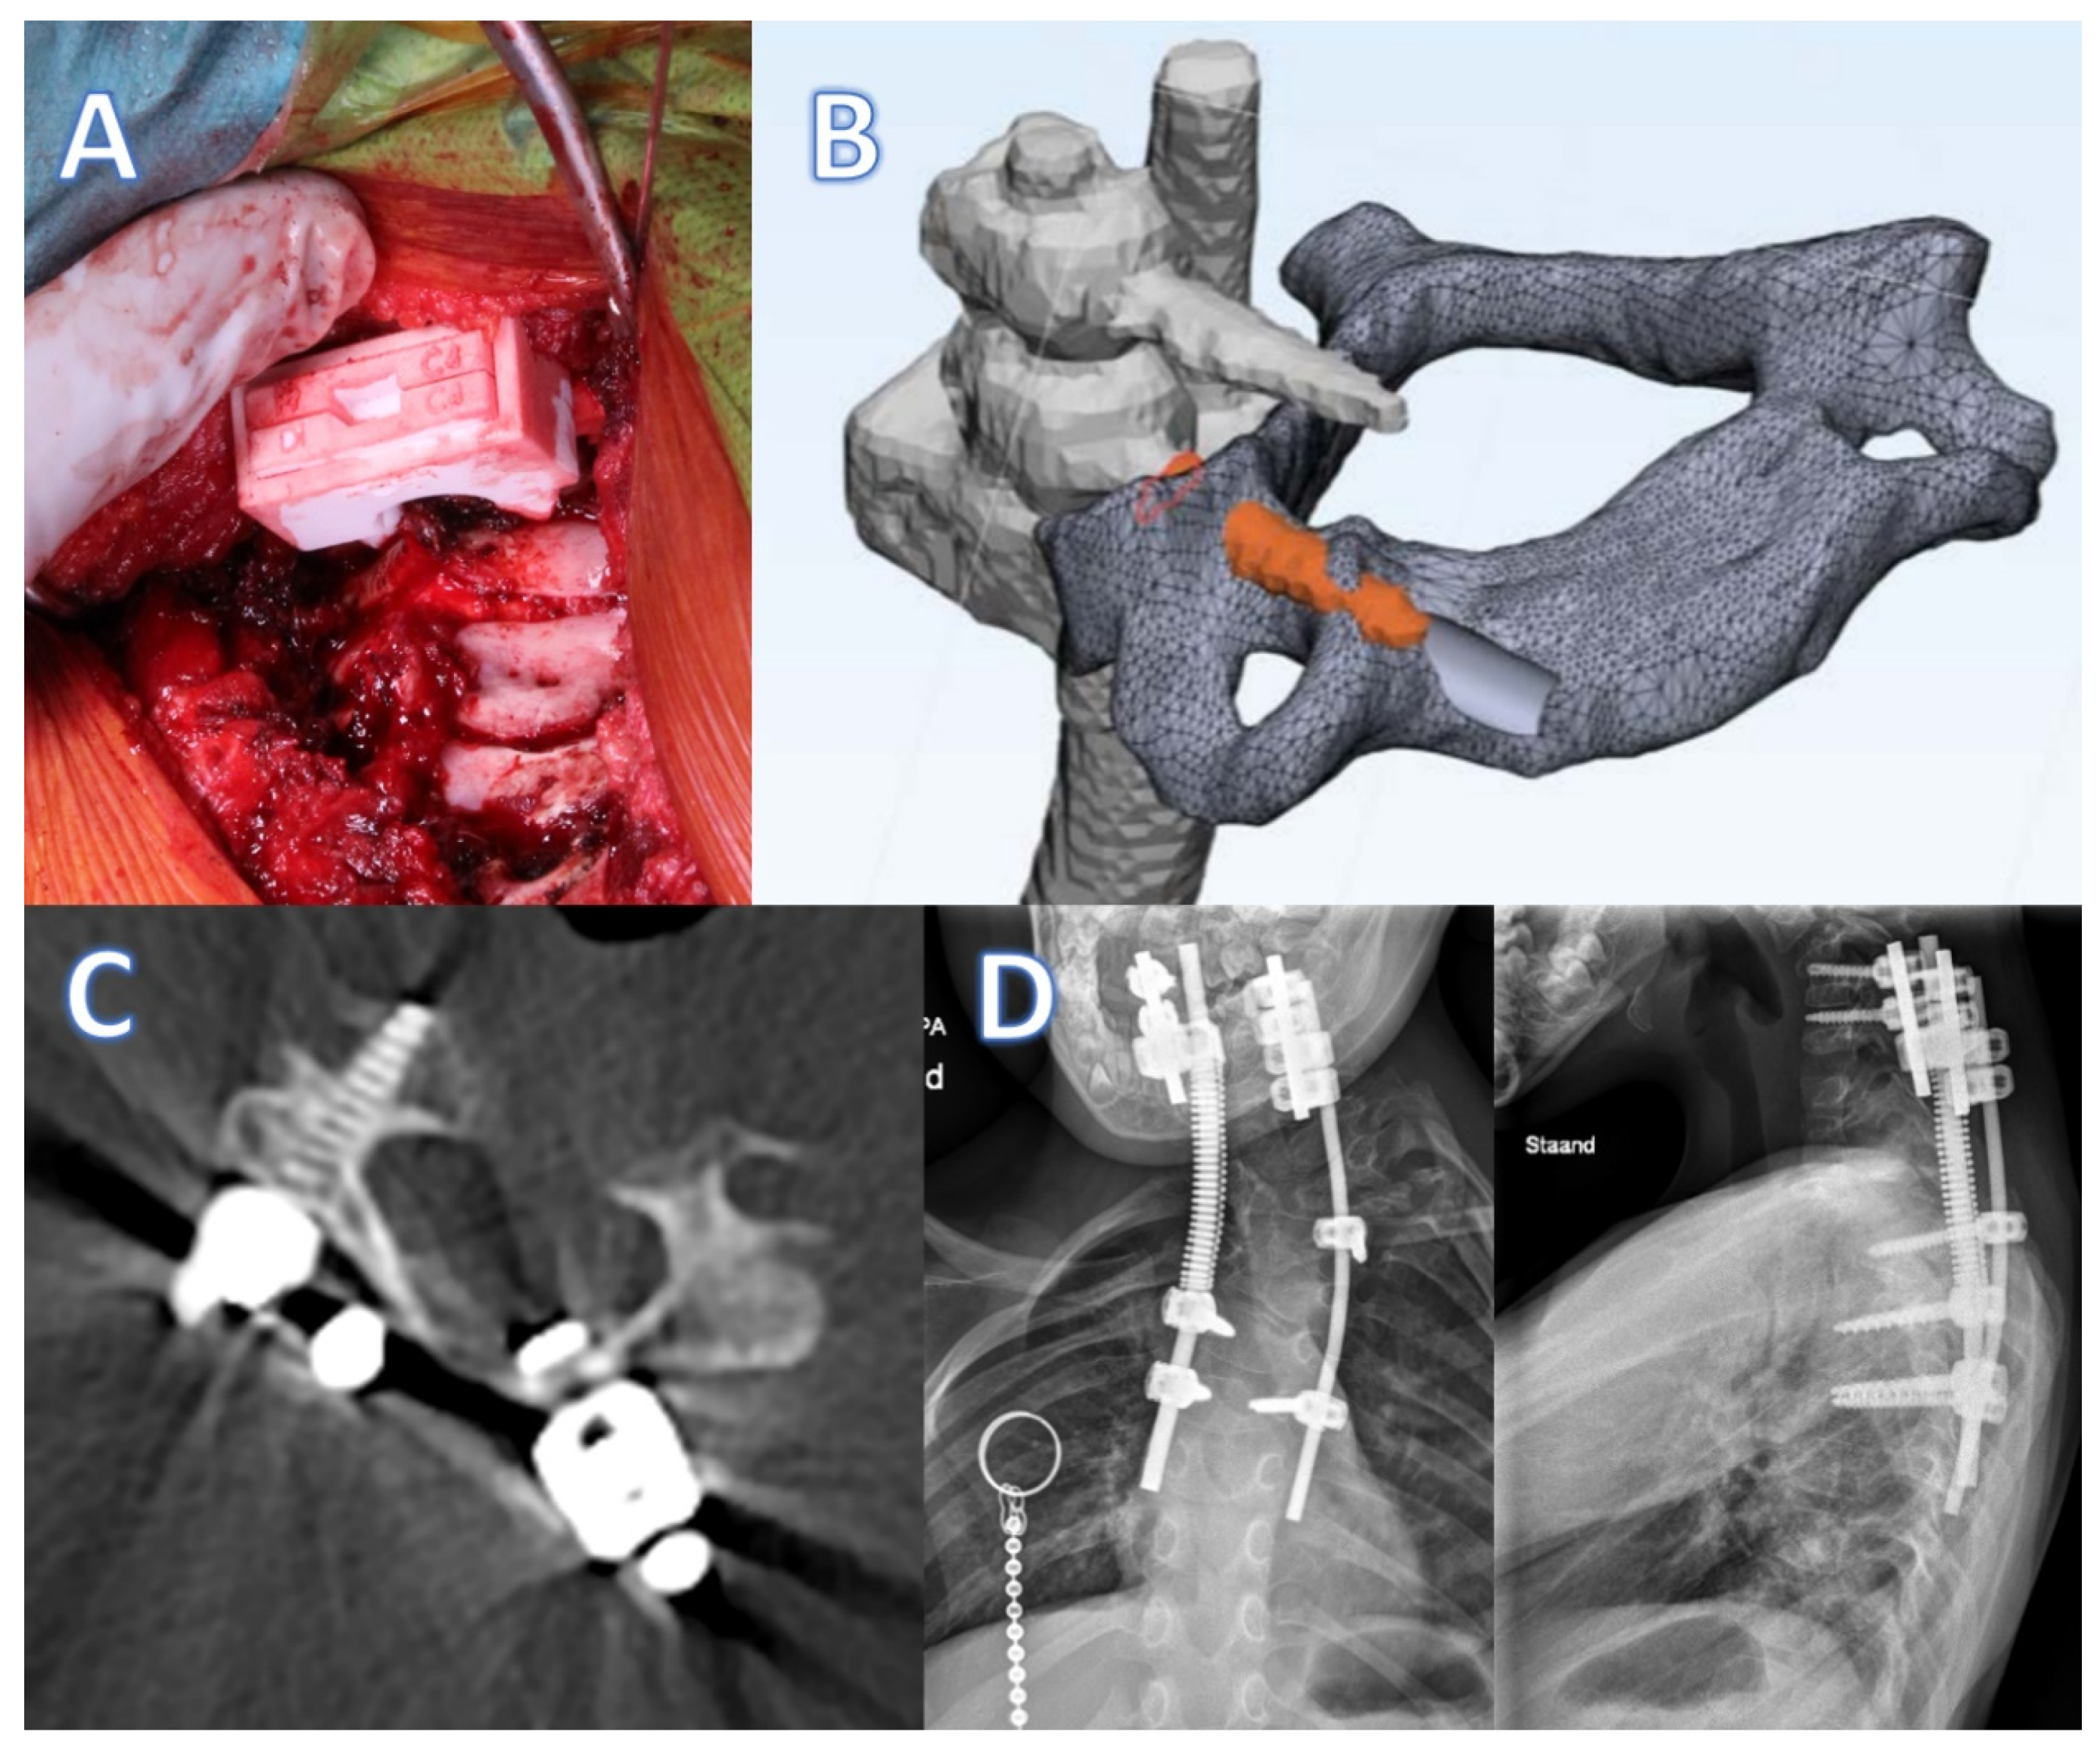

6. Device Description of Spinal Prosthesis

6.1. Anatomical Data Acquisition

6.2. Design

Implant Production

6.3. Clinical Experience with Spinal Prosthesis